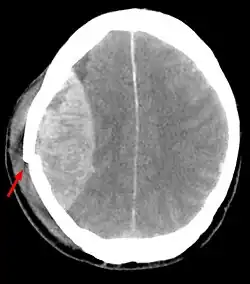

Een epidurale bloeding is een inwendige bloeding uit een hersenslagader, meestal de arteria meningea media (85-95%), die meestal ontstaat na hoofdletsel, soms met een fractuur van het slaap- of wandbeen. Bij deze bloeding hoopt zich bloed op in de ruimte tussen het schedelbot en de dura mater, het buitenste hersenvlies.

Diagnostiek vindt plaats via een CT-scan van het hoofd. Soms kan ook op een gewone röntgenfoto van de schedel een fractuurlijn in het gebied van de arteria meningea media gezien worden. De behandeling is neurochirurgisch, waarbij een luik gezaagd wordt in de schedel op de plaats van de bloeding (craniotomie), waardoor het stolsel verwijderd en de oorzaak van de bloeding verholpen kan worden.